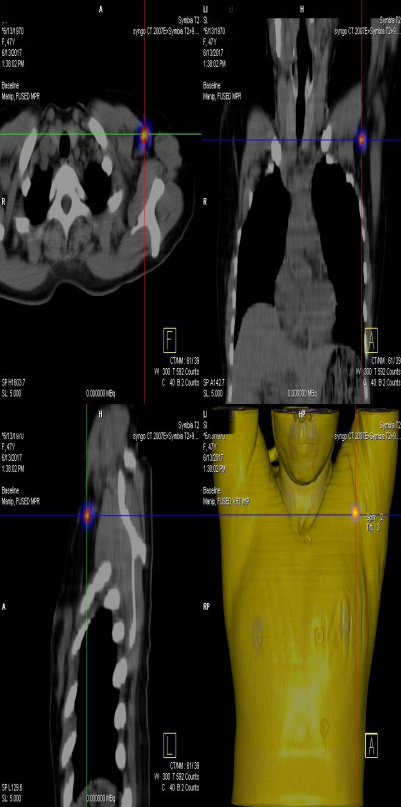

前哨淋巴結(jié)顯像技術(shù)一般在腫瘤附近注射放射性核素標(biāo)記特殊藥物,這種藥物會(huì)被前哨淋巴結(jié)攝取,存在于前哨淋巴結(jié)中。24小時(shí)之內(nèi)都可用SPECT-CT進(jìn)行前哨淋巴結(jié)顯像檢查。

找到幾個(gè)淋巴結(jié)沒有明確的限制,淋巴結(jié)核素計(jì)數(shù)小于第一個(gè)SLN計(jì)數(shù)的10%就不再是前哨淋巴結(jié)了。

患者李女士,發(fā)現(xiàn)右側(cè)乳腺腫物,來我院就診,行乳腺腫物局部擴(kuò)大切除術(shù),術(shù)后病理回報(bào):右乳腺浸潤(rùn)性導(dǎo)管癌III級(jí),伴原位癌。擬行右乳腺癌切除術(shù),提檢前哨淋巴結(jié)顯像檢查,明確有無淋巴結(jié)轉(zhuǎn)移。